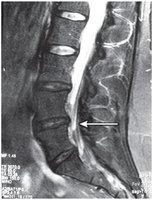

Spinal Column Pathology

Common Spinal Disorders

Herniated Disk: Protrusion of intervertebral disk, compressing spinal cord.

Abnormal Curvatures:

Kyphosis: Excessive posterior thoracic curvature.

Lordosis: Excessive anterior lumbar curvature.

Scoliosis: Lateral curvature of the spine.